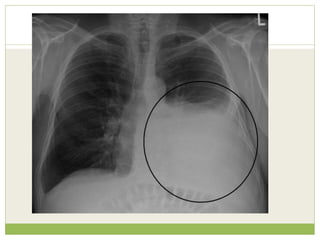

PLEURAL EFFUSION

๏‚— Pleural effusion is excess fluid that accumulates

๏‚— Excessive amounts of such fluid can impair

๏‚— Four types of fluids can accumulate in the pleural